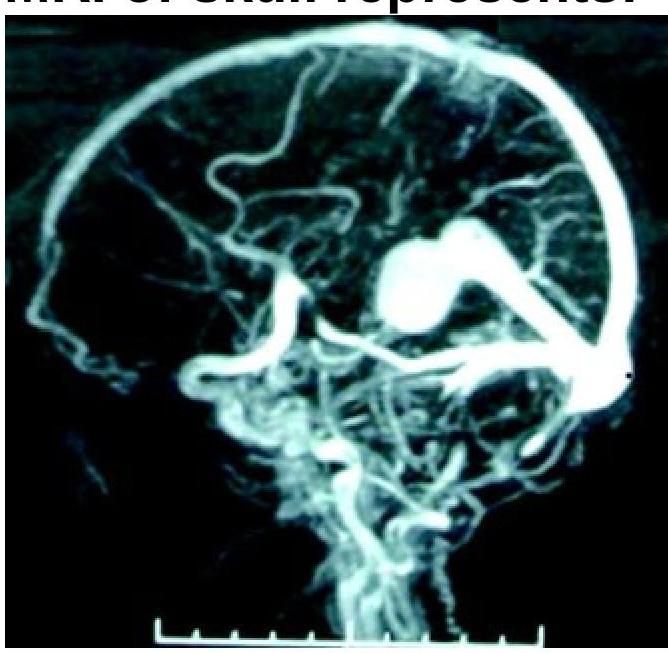

Question 8: What condition is shown in the MR angiogram of the skull?

- A. Vein of Galen malformation (Correct Answer)

- B. Dandy-Walker malformation

- C. Pneumocephalus

- D. Crouzon syndrome

Explanation: ***Vein of Galen malformation*** - The image provided is an **MR angiogram (MRA)**, which clearly shows a **large, dilated vein of Galen**. This is the characteristic appearance of a Vein of Galen malformation. - This congenital vascular malformation involves a direct artery-to-vein shunt, leading to the characteristic aneurysmal dilatation of the vein. *Dandy-Walker malformation* - This is a congenital brain malformation characterized by **agenesis or hypoplasia of the cerebellar vermis** and cystic dilation of the fourth ventricle. - While it affects brain structures, it does not involve the type of vascular abnormality seen in the image. *Pneumocephalus* - **Pneumocephalus** refers to the presence of **air within the intracranial cavity**, often due to trauma or surgery. - It would appear as dark areas on imaging, representing air, not the bright, dilated vascular structures seen here. *Crouzon syndrome* - **Crouzon syndrome** is a genetic disorder characterized by **craniosynostosis**, which is the premature fusion of skull sutures. - This condition primarily affects bone growth and skull shape, with no direct involvement of the cerebral vasculature as depicted in the MRA.